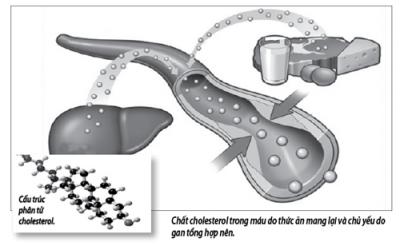

Mỡ trong máu cao là tình trạng rối loạn chuyển hoá lipid. Chất mỡ trong cơ thể chủ yếu là cholesterol và triglyceride, khi có nồng độ cao trong máu sẽ gây xơ vữa mạch máu dẫn đến tai biến mạch máu não và nhồi máu cơ tim. Chi tiết »